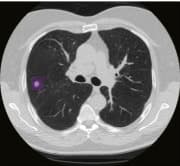

๐ฉป Time to Diagnosis: Predictive Modeling for Lung Cancer Screening

We used low-dose CT scans from the National Lung Screening Trial (NLST) to predict lung cancer risk over time. Building on the Sybil model for time-to-event prediction, we compared various CNN encoders (ResNet, DenseNet), pretrained on both ImageNet and RadImageNet, to study how medical vs. general pretraining affects performance. We visualized learned features with t-SNE and assessed models using ROC and C-index metrics. A deep dive into model design, survival analysis, and AI for early cancer detection.